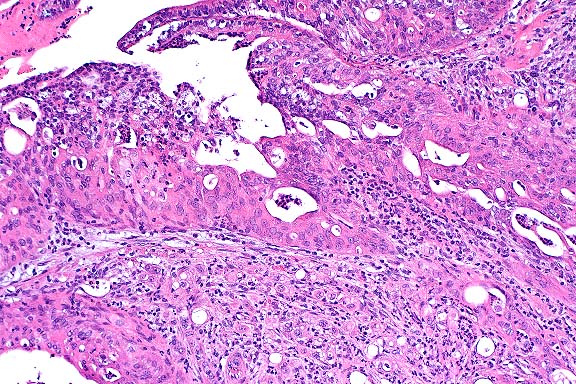

40x

obj

- Case 15-2. Seminal vesicle. Pleomorphic tumor cells,

which are admixed with neutrophils in the submucosa may contain

multiple nuclei or variably sized vacuoles which displace the

nucleus peripherally (signet ring cells).

- As noted by the contributor, distinguishing between adenocarcinomas

of the coagulating gland and seminal vesicle may be difficult,

especially when the tumor is large and involves adjacent organs.

Determining the site of origin grossly is often troublesome,

especially when tumors are located in the proximal part of the

seminal vesicle adjacent to the dorsolateral prostate. Histologically,

both tumors feature a glandular pattern with prominent stroma.

- Most conference participants favored seminal vesicle as the

primary site of origin, because many sections contain areas in

which there appears to be transition from normal glandular epithelium

of the seminal vesicle to the neoplasm, although this finding

is not present in all histologic sections. Other histologic features

of the tumor consistent with seminal vesicle origin include elongated

fronds of basophilic epithelium, small amounts of brightly eosinophilic

secretory product within glandular structures, and the scirrhous

reaction. The coagulating gland contains smaller papillary projections

and forms a pale, eosinophilic secretory substance compared to

the seminal vesicle; the epithelium is lightly eosinophilic rather

than basophilic. Tumors of the coagulating gland tend to be smaller

and less schirrhous than those of the seminal vesicle.

- While rats have a high incidence of spontaneous prostatic

tumors, spontaneous neoplasms of the seminal vesicles are rare,

with fewer than ten cases reported. Neoplasia of the seminal

vesicles is rare in humans and domestic animals as well. Experimentally,

neoplasia of the seminal vesicle can be induced in rats by exposure

with several carcinogenic agents, including N-methylnitrosourea

and irradiation. Because of the scarcity of reports of spontaneous

seminal vesicle neoplasia in rats, little is known about the

biological behavior of these tumors. A recent case report of

a seminal vesicle adenocarcinoma in a Fischer 344 rat described

a pleomorphic tumor with numerous mitoses but no observed metastases.